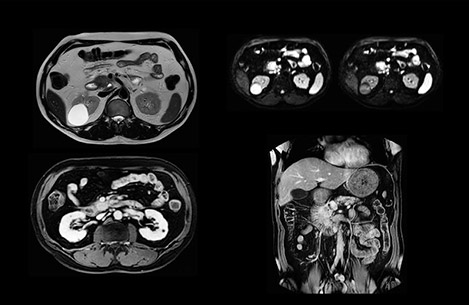

An efficient comprehensive liver exam

“Our liver exams are quite fast,” says Dr. Baumann. “If the patient tolerates it, we use an arms-up position to reduce the FOV and speed up the exam with dS SENSE.”

“We acquire one transversal high resolution T2-weighted sequence with 3 mm slice thickness, for example for pancreas or liver lesions. Then we also add a T2 fat suppressed MultiVane XD SPIR sequence. We perform these two routinely in our liver imaging. We use high dS SENSE factors to significantly shorten scan times to 2-4 minutes, which can improve our protocol; it’s a very robust scan.”

“We include mDIXON for the dynamic sequences because of the robust and homogeneous fat suppression we get with that. We had been using eTHRIVE, but we are now quite happy with mDIXON. Sometimes we use a medication to calm the bowels, to further improve the image quality.”